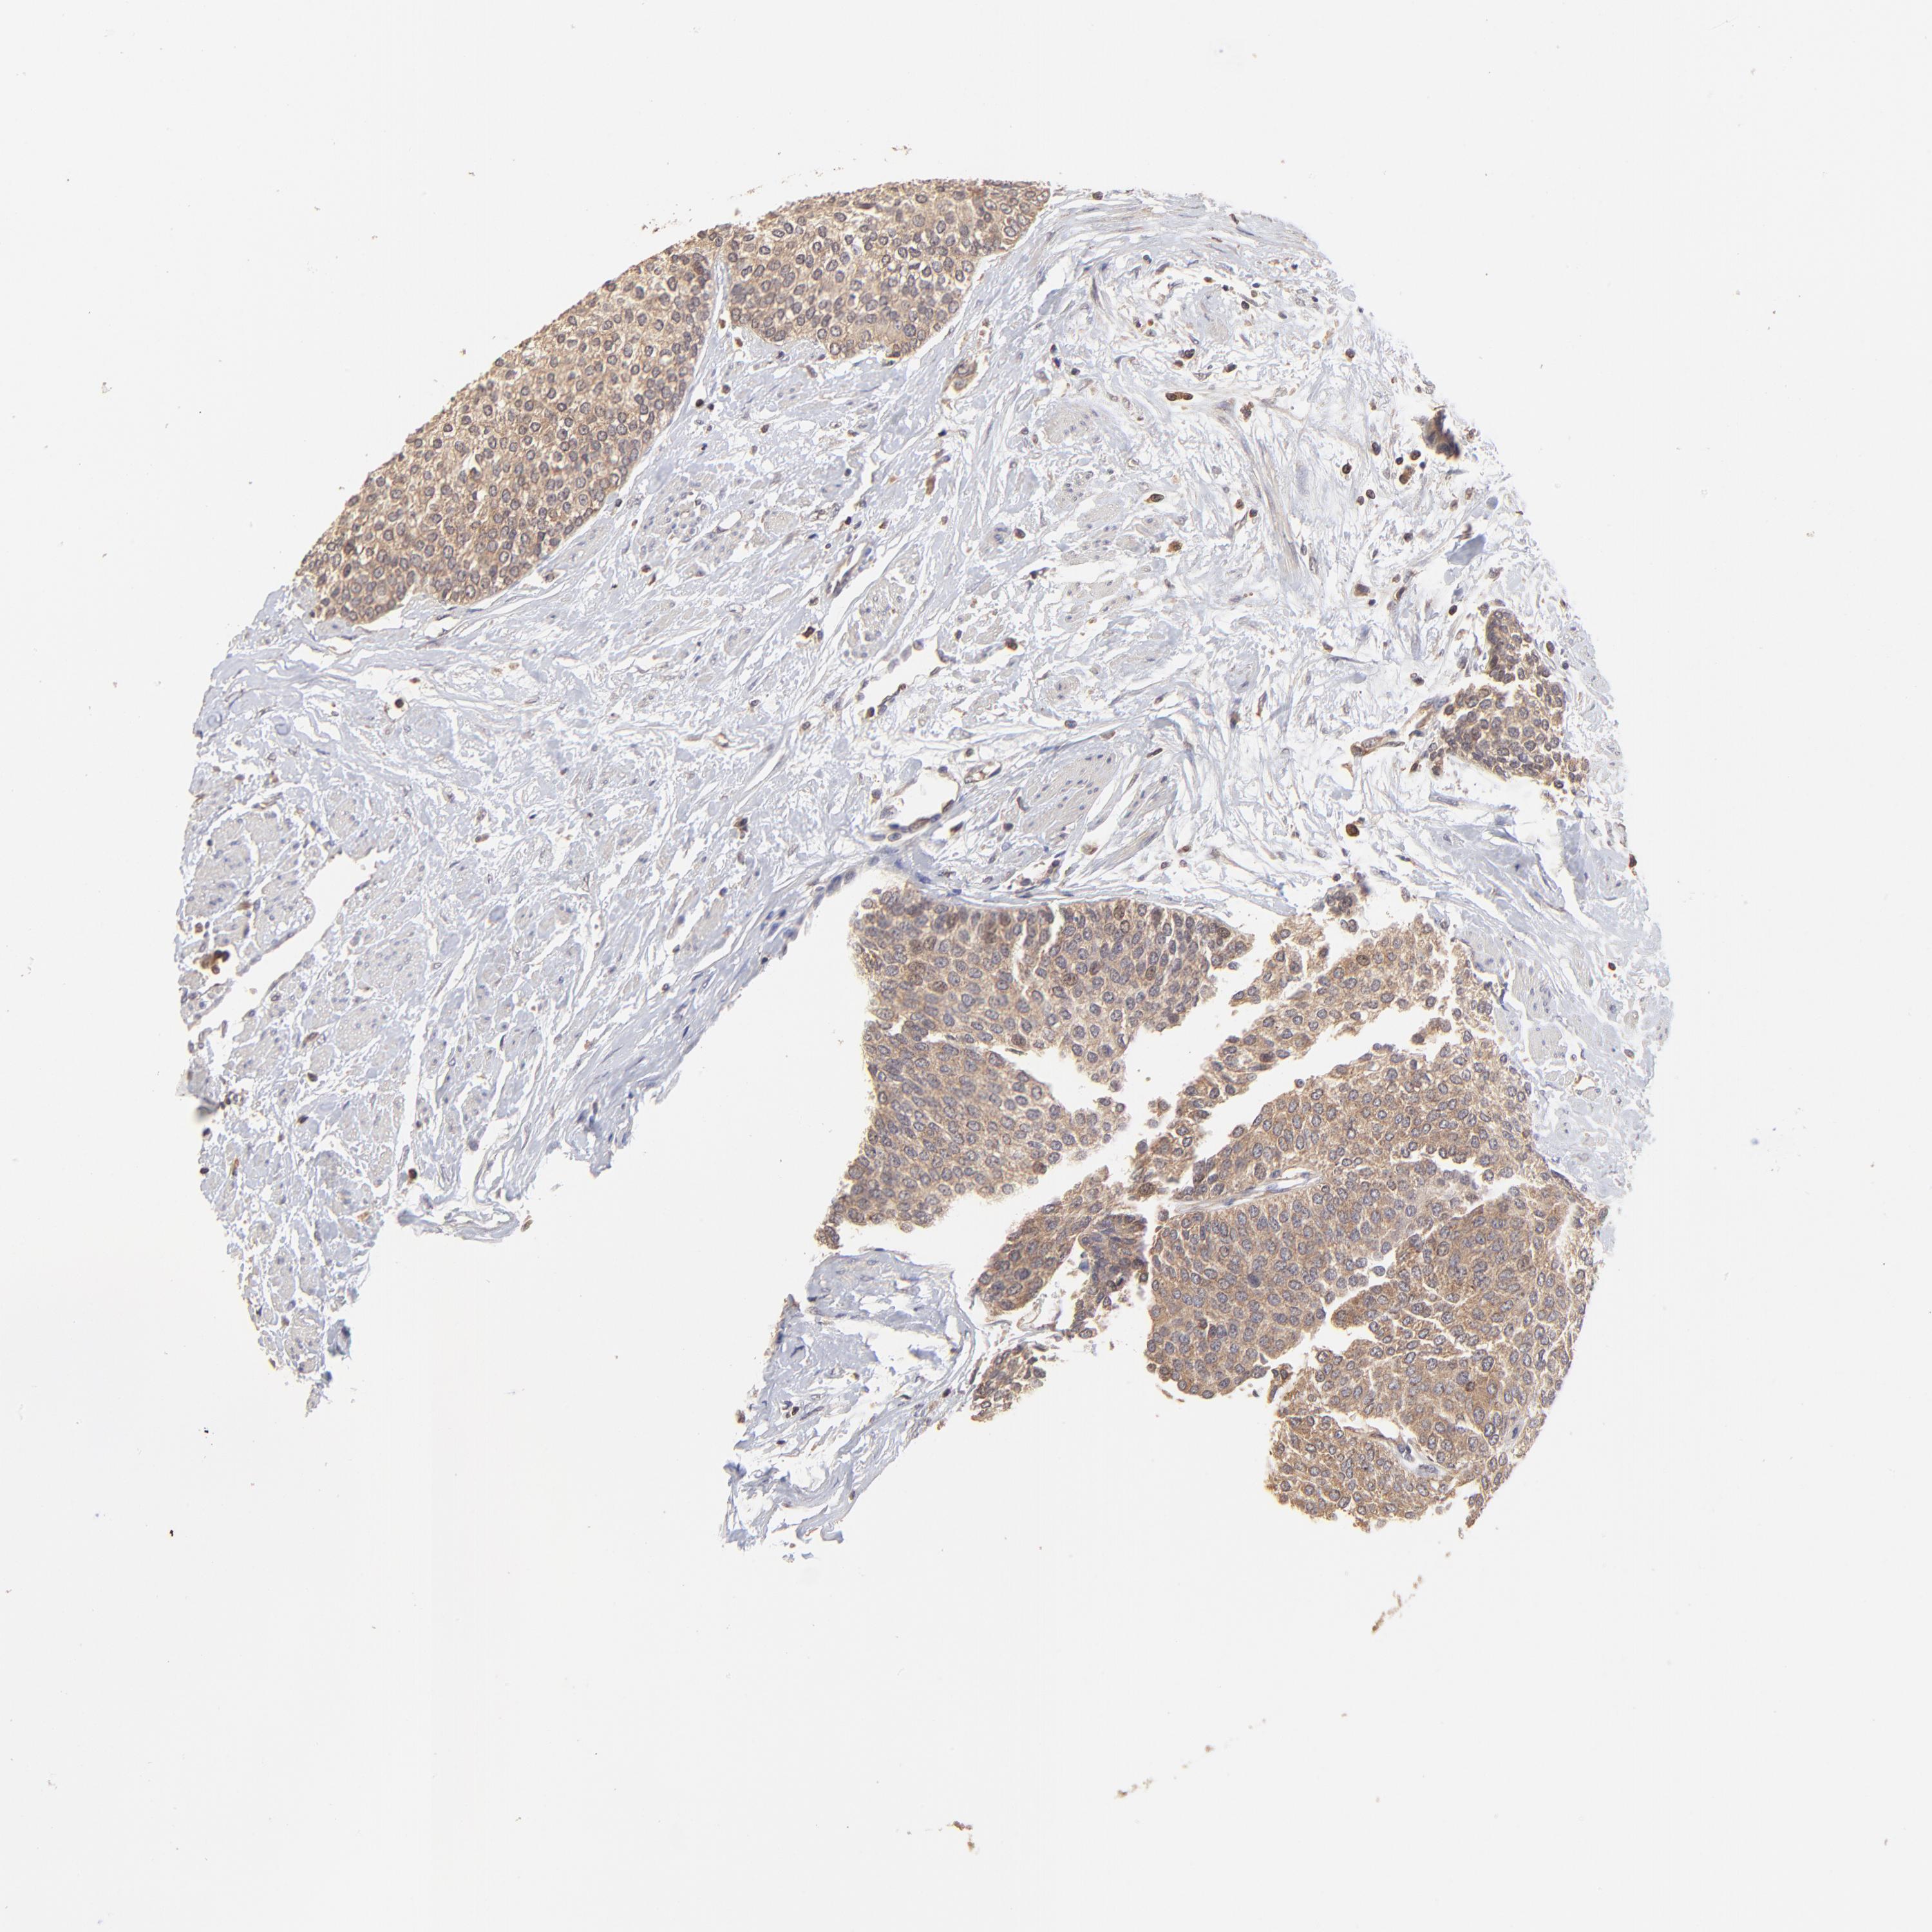

UROTHELIAL CANCER - Protein expressioni

A mouse-over function shows sample information and annotation data. Click on an image to view it in a full screen mode. Samples can be filtered based on level of antibody staining by selecting one or several of the following categories: high, medium, low and not detected. The assay and annotation is described here.

Antibody stainingi

Antibody staining in the annotated cell types in the current human tissue is reported as not detected, low, medium, or high, based on conventional immunohistochemistry profiling in selected tissues. This score is based on the combination of the staining intensity and fraction of stained cells.

Each image is clickable and will lead to virtual microscopy that enables deeper exploration of all samples and also displays staining intensity scores, fraction scores and subcellular localization as well as patient and tissue information for each sample.

Antibody HPA003086

Staining

High

Medium

Low

Not detected

Intensity

Strong

Moderate

Weak

Negative

Quantity

>75%

75%-25%

<25%

None

Location

Nuclear

Cytoplasmic/membranous

Cytoplasmic/membranous,nuclear

Urothelial carcinoma, High grade